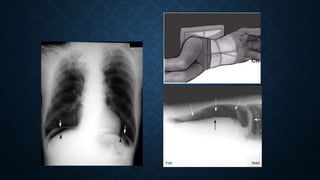

IMAGING STUDIES

A. Plain Chest X-Ray Studies:

• lower lobe pneumonia or ruptured esophagus

• An elevated hemidiaphragm or pleural effusion

• In CXR Subdiaphragmatic air(Pneumoperitoneum) more sensitive

than abdominal plain films for free intraperitoneal air.

X RAY CONTD.

Pneumoperitoneum: usually by suggests a perforated viscous

1 ml air in peritoneum produce pneumoperitoneum in upright CXR

5-10 ml air in peritoneum produce pneumoperitoneum in lateral decubitus position

(after 10 minutes)